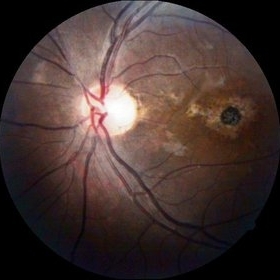

Age-Related Macular Degeneration

Sep 10 2014 by Mehul A Shah

65-year-old female presented with sudden loss of vision.

Photographer: Drashti Netralaya, Dahod

Imaging device: FF 450

Condition/keywords: age-related macular degeneration (AMD)